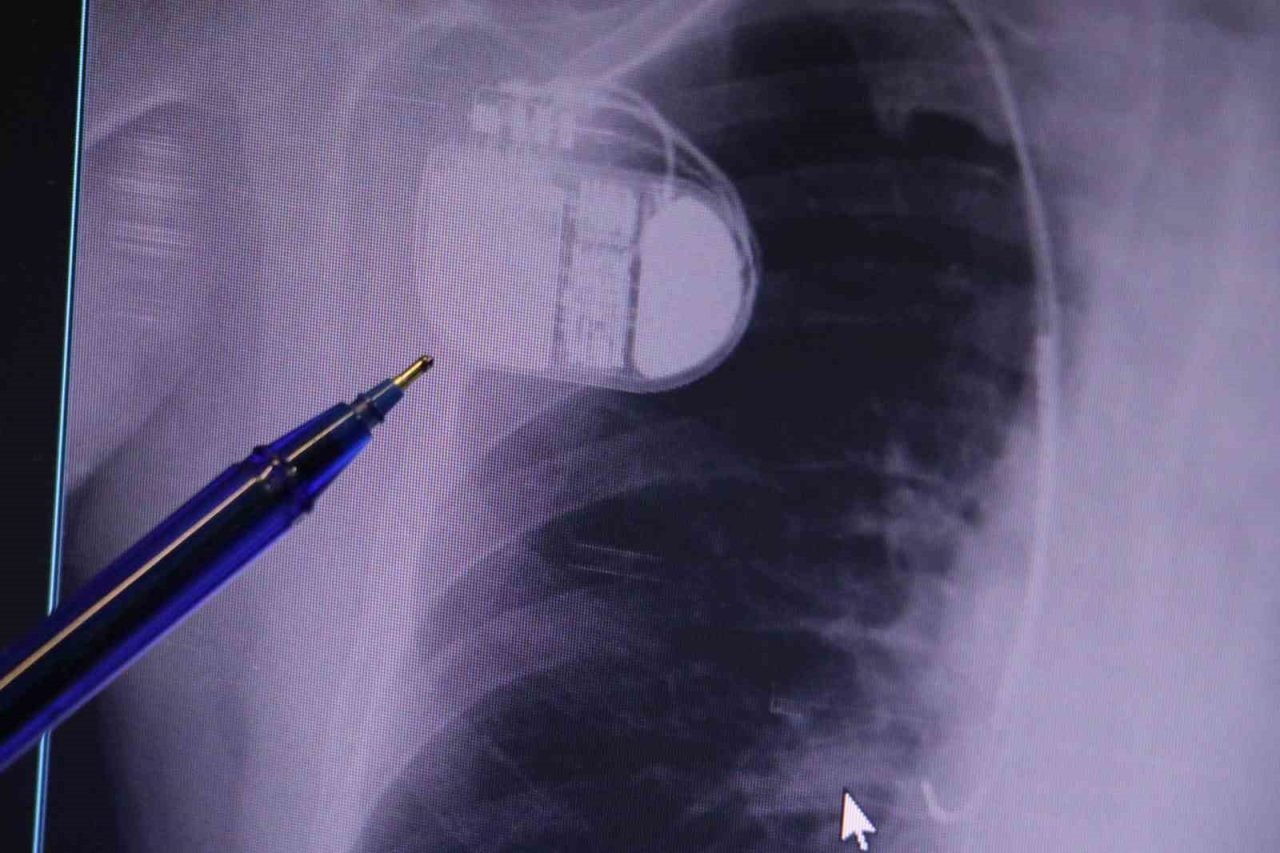

Kalp pilleri ile MR cihazına girilebileceğini belirten Erdoğu, “Çok büyük bir ameliyat değil ama yine de ciddi bir cerrahi işlem. Kalp pili, tıpta son 30 yılda yaşanan gelişmelerden en büyüğü. Bir bilgisayarın küçültülüp insan vücuduna konulmuş hali aslında. İnsan ömrünü ciddi oranda uzatan bir tedavi. İnsanlar bir şokla hayata tutunurken, pil olmasaydı öleceğini düşündüğümüz birçok hastamız var. Kalp pilinin bu özelliği, uygun hastalarda ciddi oranda ani ölümü engelliyor. Hastanın başına gelecek bir kalp durması durumunda yanında bir sağlıkçı yoksa, onun ritmini düzeltecek defibrilatör cihazı yoksa hastayı hayatta tutmak mümkün değil. Uygun endikasyonlarda kalp pili olduğu zaman, pil hastaların ritmini algılıyor ve acilde yapılan şoklamayı yaparak hastayı hayata döndürüyor. Kalp pillerinde yeni teknolojilerle MR’a girmek mümkün, tomografiye zaten girebiliyorlar. Tarama cihazlarından geçmelerini uygun görmüyoruz. Bu tarz durumlarda hastalarımız ’kalp pilim var’ dediğinde muaf tutuluyorlar. Kalp pilleri ciddi teknolojik cihazlardır. Vücudun içindeki titreşimi, örneğin mikser kullanmak, kolunu sallayacak herhangi bir eylem kalp pilinde olumsuz etki oluşturabilir. Soğuk havalarda vücutta oluşan ciddi titremeler kalp pilinin hafızasını karıştırıp kalbin durduğunu düşündürebilir ve gereksiz şoklama yapabilir. Bu tarz kişilerin soğuk havalarda daha temkinli olması gerekir” diye konuştu.